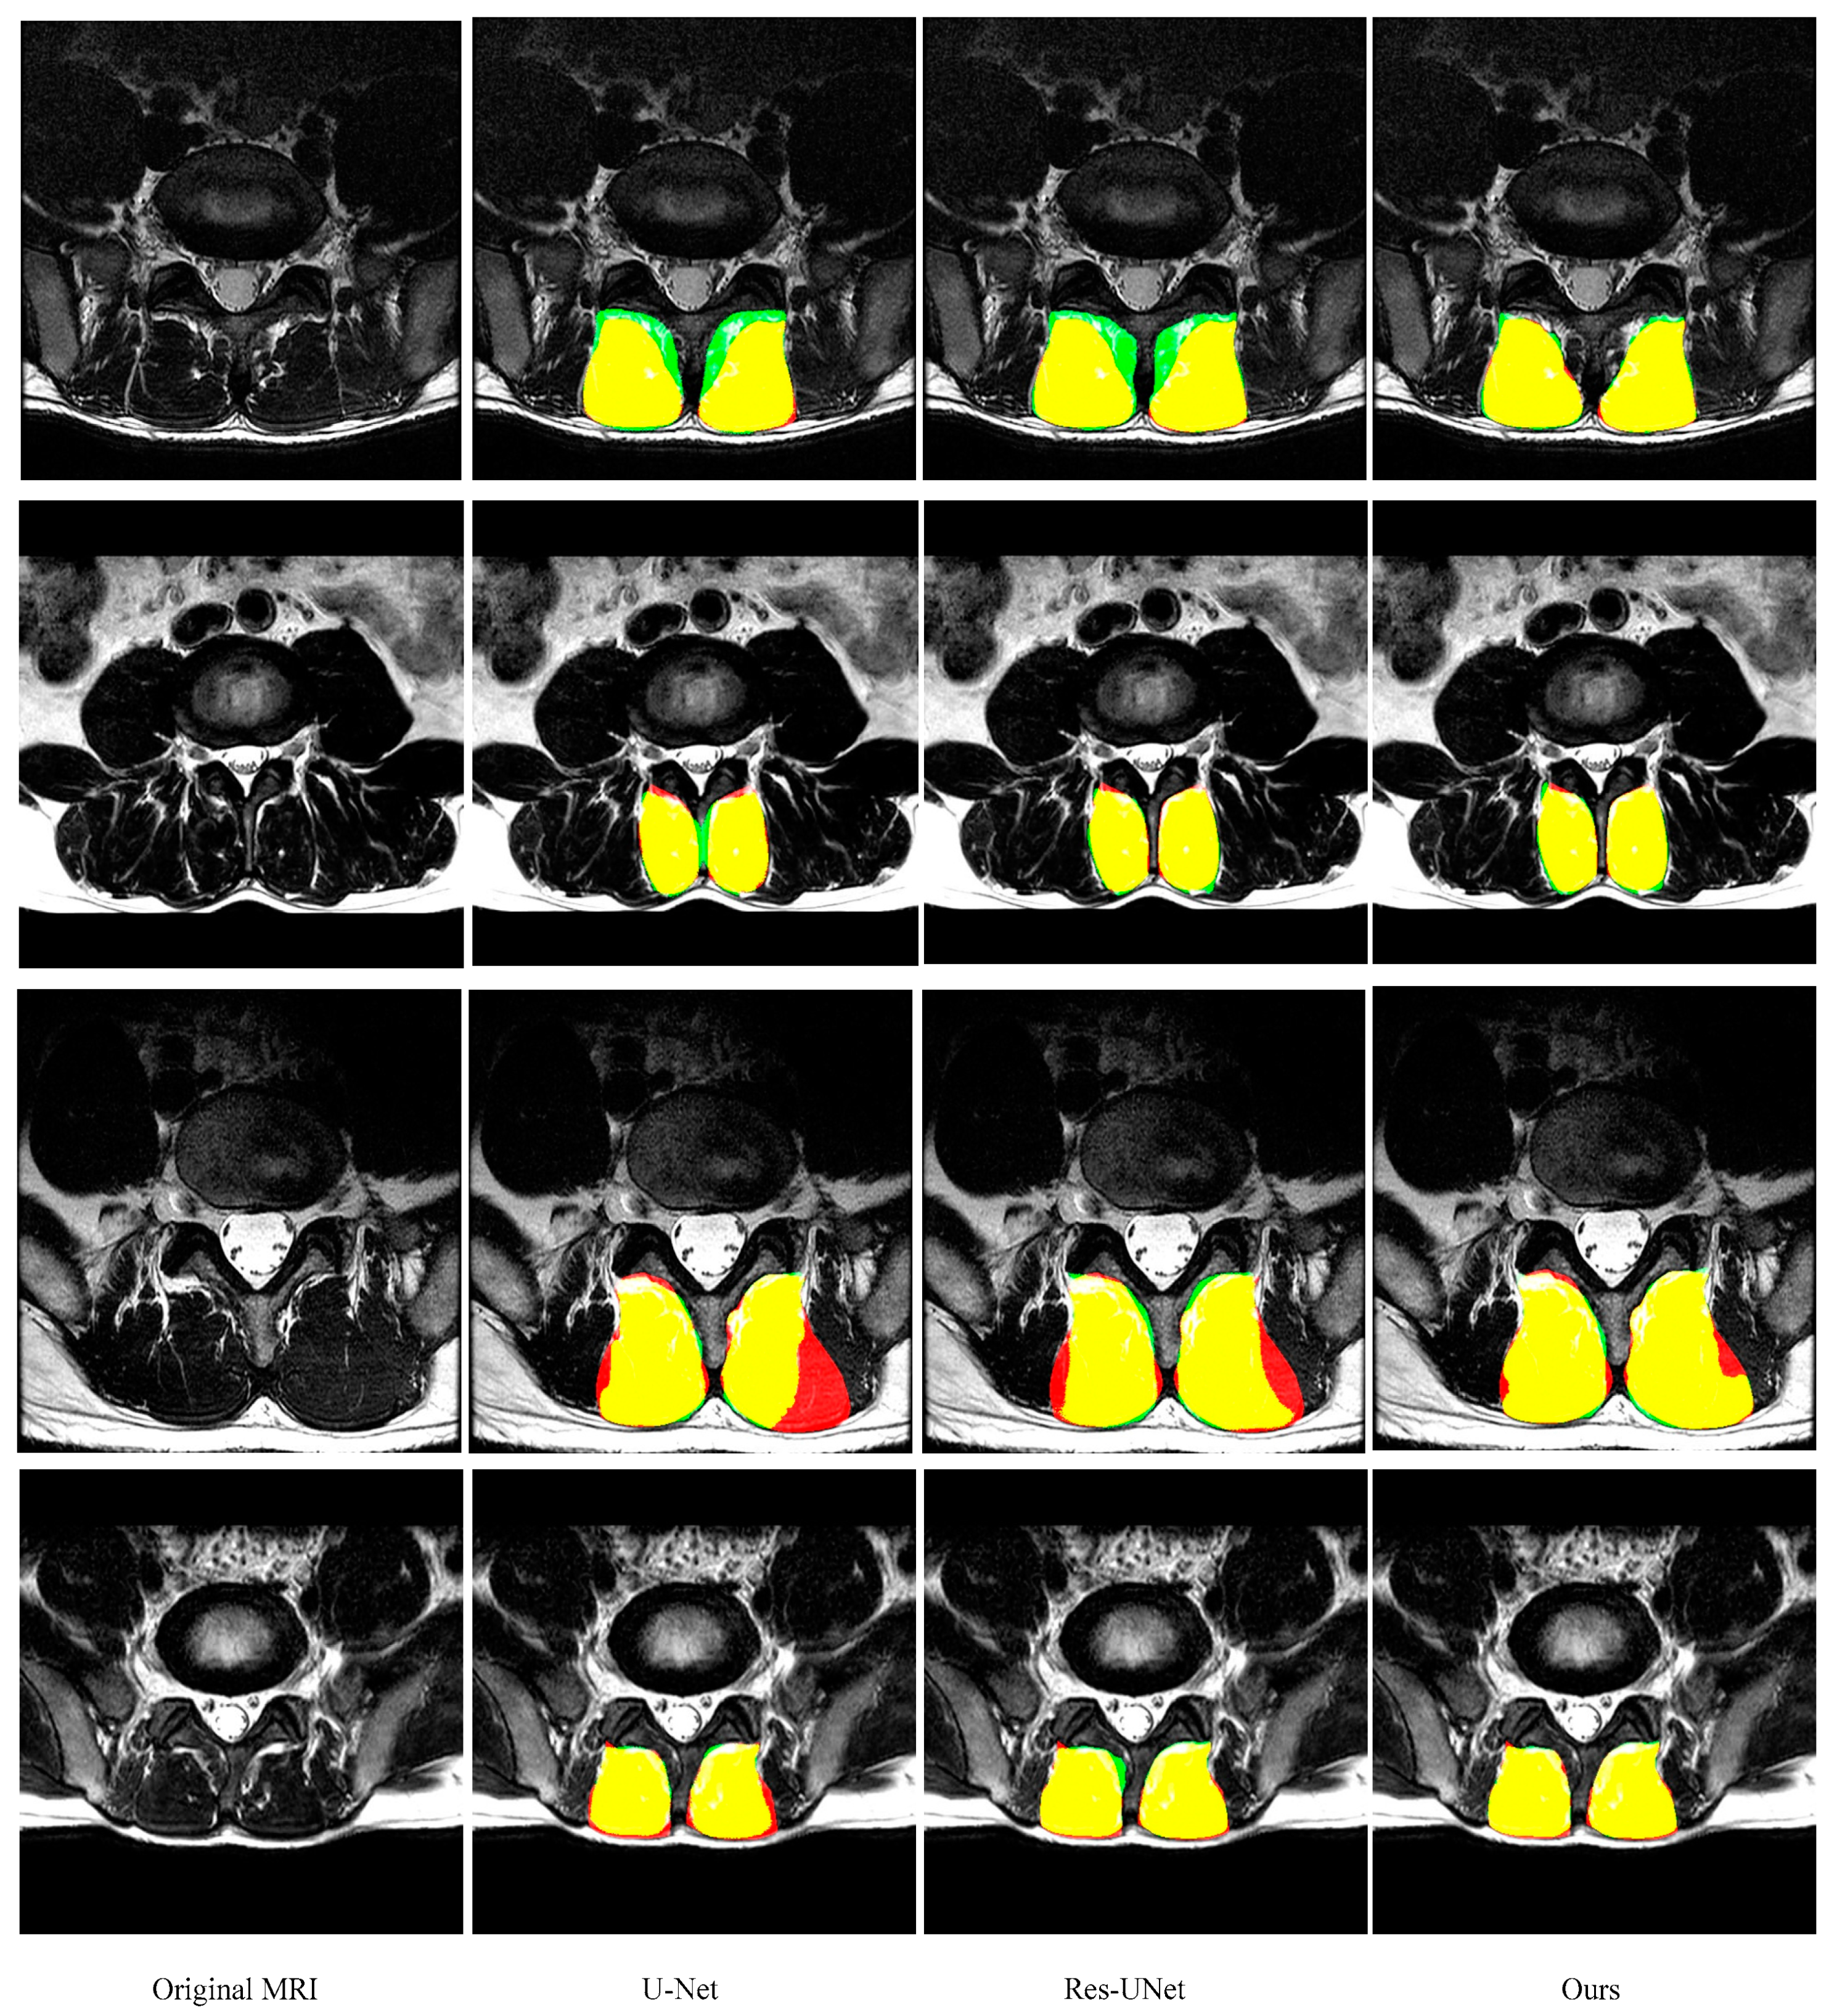

3.5. Comparison with other State-of-the-Art Methods